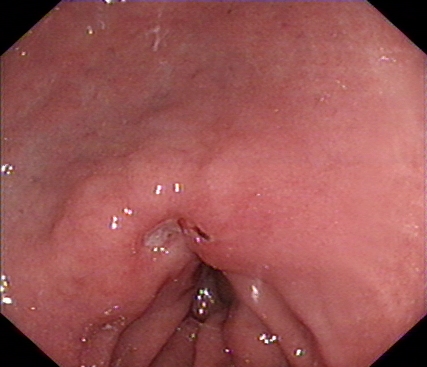

2020年1月,元旦刚过,大家都还沉浸在新年的喜悦中,来自隆安县的张阿姨一家却一筹莫展,张阿姨今年55岁,半年前开始出现上腹部胀痛不适,在当地医院一直按“慢性胃炎”服用中药及西药治疗,症状时好时坏。为了进一步治疗,来到我院就诊,内镜中心袁海锋主任亲自为其进行了无痛胃镜检查,经认真仔细观察发现胃内一处凹陷型病变,进一步行精细胃镜检查后,初步判断为早期胃癌病灶,而且病变侵犯深度局限在粘膜层内。经过与张阿姨及家属详细沟通后,决定用内镜下微创手术为其治疗。在内镜下确定病变边界后,顺利行内镜下粘膜剥离术(ESD)将病变完整切除。术后标本病理提示:早期胃癌(中分化管状腺癌)。治疗后一周,恢复良好,顺利出院,至今随访未诉明显不适。对于张阿姨一家来说,得了胃癌很不幸,但不幸中的万幸,她的胃癌被我们早期及时发现并完成了内镜下切除,避免进展为中晚期胃癌,使原本不富裕的家庭再雪上加霜。

图1 胃镜下早癌病灶